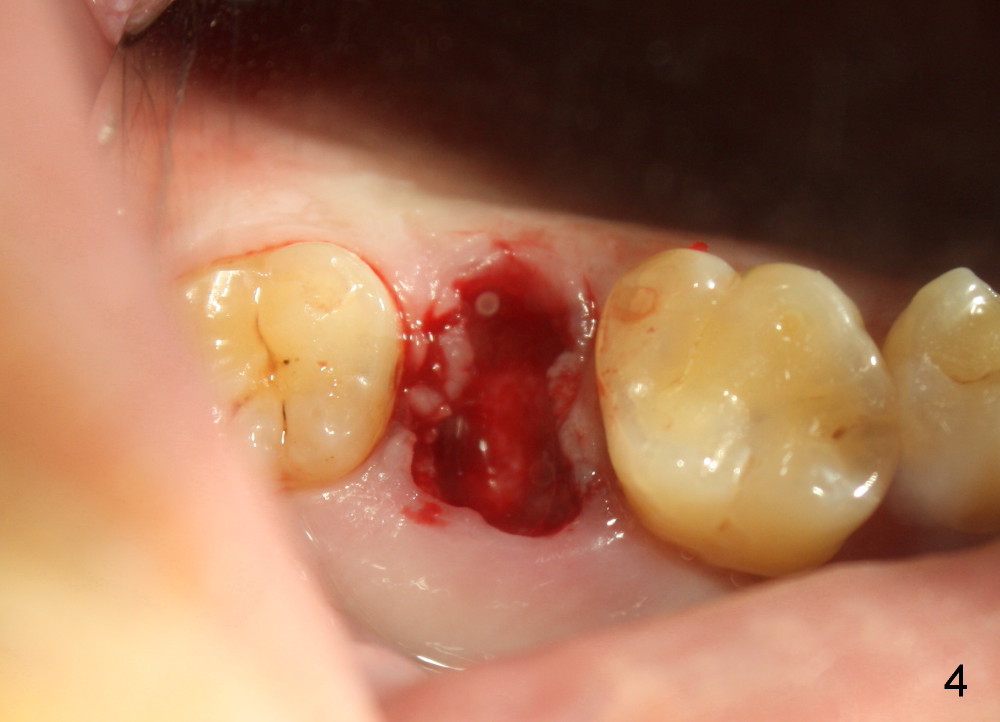

A 42-year-old man is afraid of dentistry. Residual roots of #2 remain untreated for at least 2.5 years (Fig.1). Both the mesiodistal space and the height are limited and unfavorable to restoration (Fig.2,3). Finally he agrees to have treatment, since the tooth #15 is worn so much that it is sensitive to mastication. When the tooth #2 is extracted, the socket is triangular without septum (Fig.4); the bottom of the socket is flat and easy for osteotomy. A 5x17 mm tap has obtained stability once it is placed ~ 14 mm deep (Fig.5). A 5x14 mm implant is placed with insertion torque > 60 Ncm (Fig.6 I), followed by placement of 4x3 mm abutment (A).

To prevent the narrow spaces from getting worse during osteointegration, an immediate provisional is to be fabricated. There is not enough occlusal clearance when the abutment is reduced ~1.5 mm. The abutment is removed; the implant is placed ~ 1 mm deeper with primary stability. Then the occlusal clearance is sufficient; the provisional is made. Mixture of autogenous bone, allograft and Osteogen is placed in the remaining buccal and lingual sockets (Fig.7 *). The provisional is temporarily cemented (Fig.8 P), which keeps the bone graft in place.